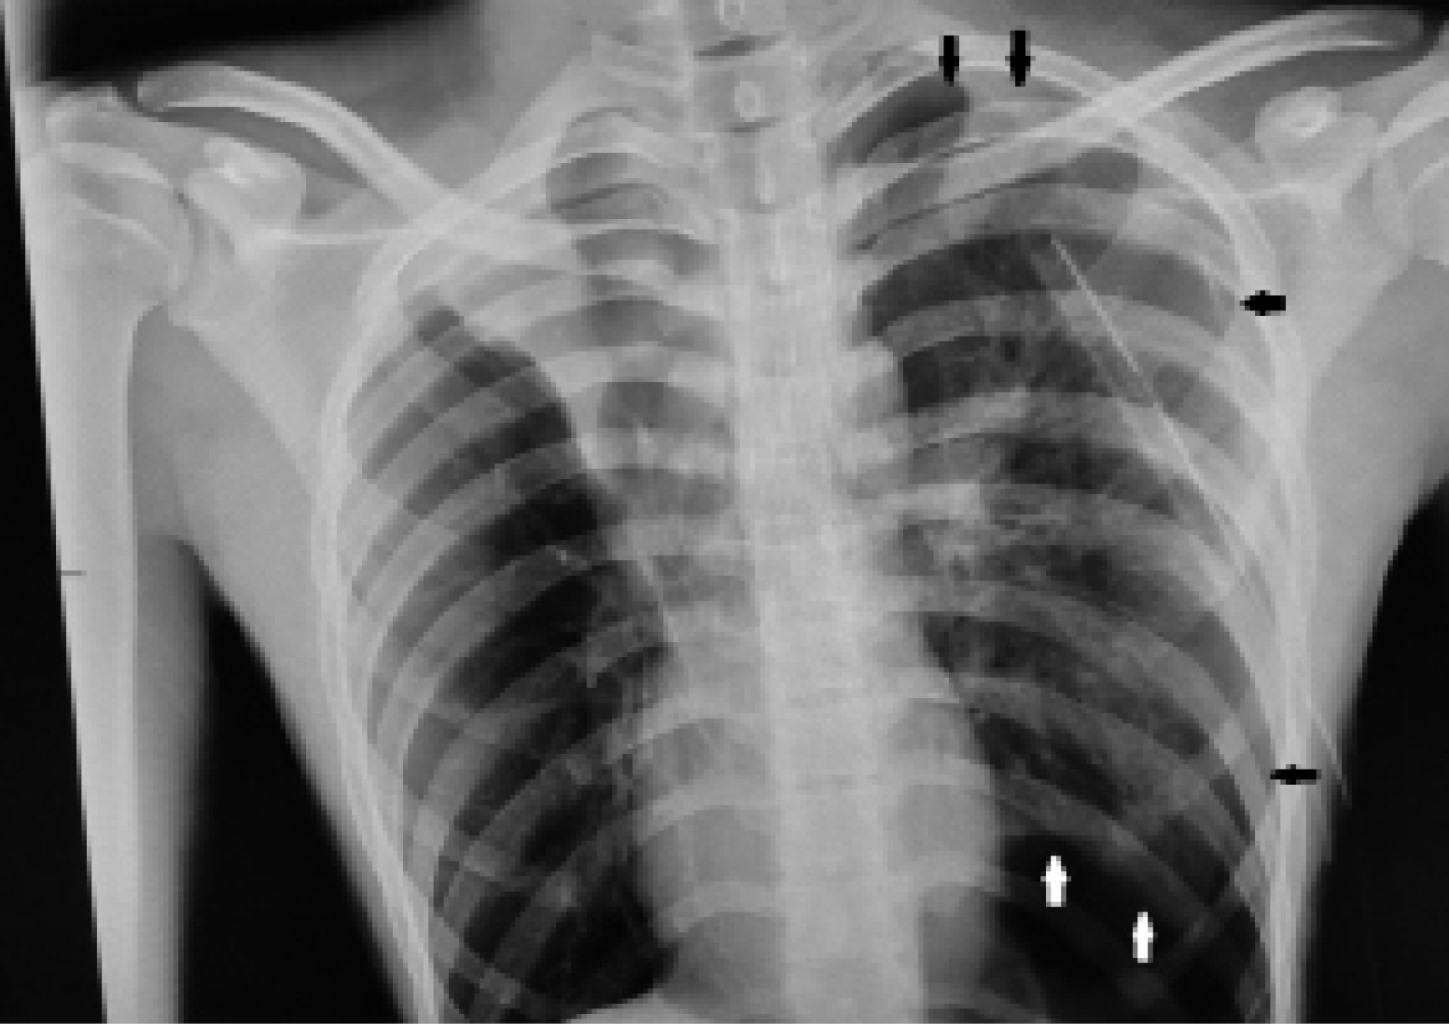

Three weeks later, he came to the emergency department referring a two-day evolution of pain in the left hemithorax, of sudden onset, transfixing, as well as dyspnea at rest; the physical examination revealed hypoventilation of the left hemithorax and hyper resonance to percussion. The X-ray showed recurrent pneumothorax (Figure 1) and an endo pleural probe was placed. Adequate pulmonary expansion was seen on X-ray (Figure 2). Seven days later the patient underwent a seal pleural probe test, presenting dyspnea and chest pain. A control X-ray showed recurrent left pneumothorax (Figure 3), so a CT scan was requested, showing persistent pneumothorax, and left apical bulla, so a surgical protocol for thoracoscopy was initiated.

Figure 1